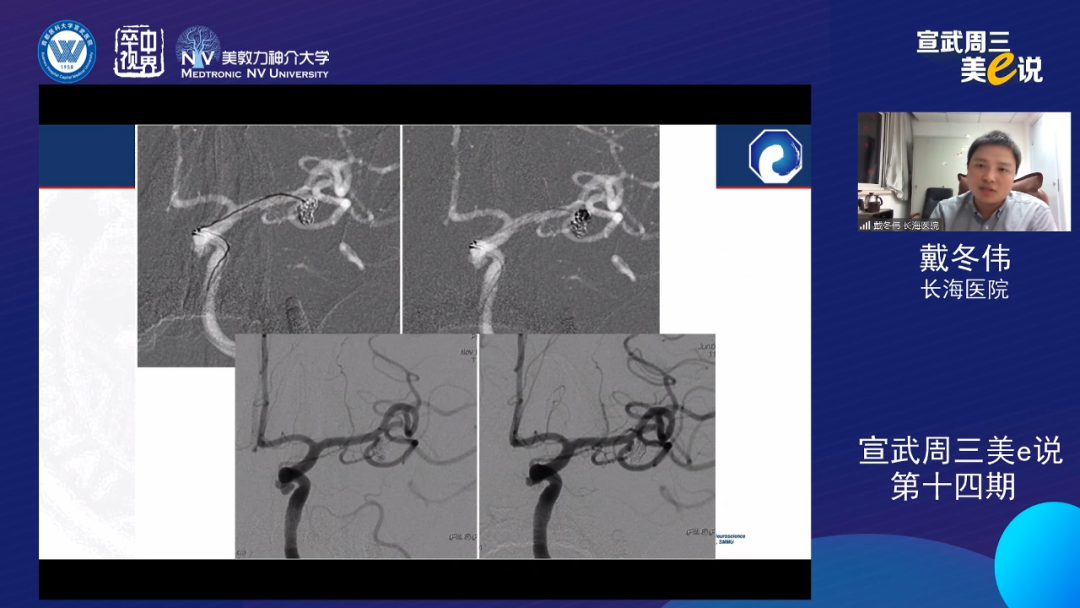

戴冬伟

上海长海医院

戴冬伟教授通过多个病例介绍了双微导管技术在各种复杂动脉瘤中的应用,体现了双微导管技术对于保护分支血管,避免支架抗聚,以及栓塞多子囊不规则动脉瘤的独特优势。同时戴教授也谈到了双微导管技术的局限性,包括瘤颈致密栓塞可能不足,可能导致弹簧圈部分突入载流动脉等。相对支架而言,双微导管技术可能需要更高的操作技巧。